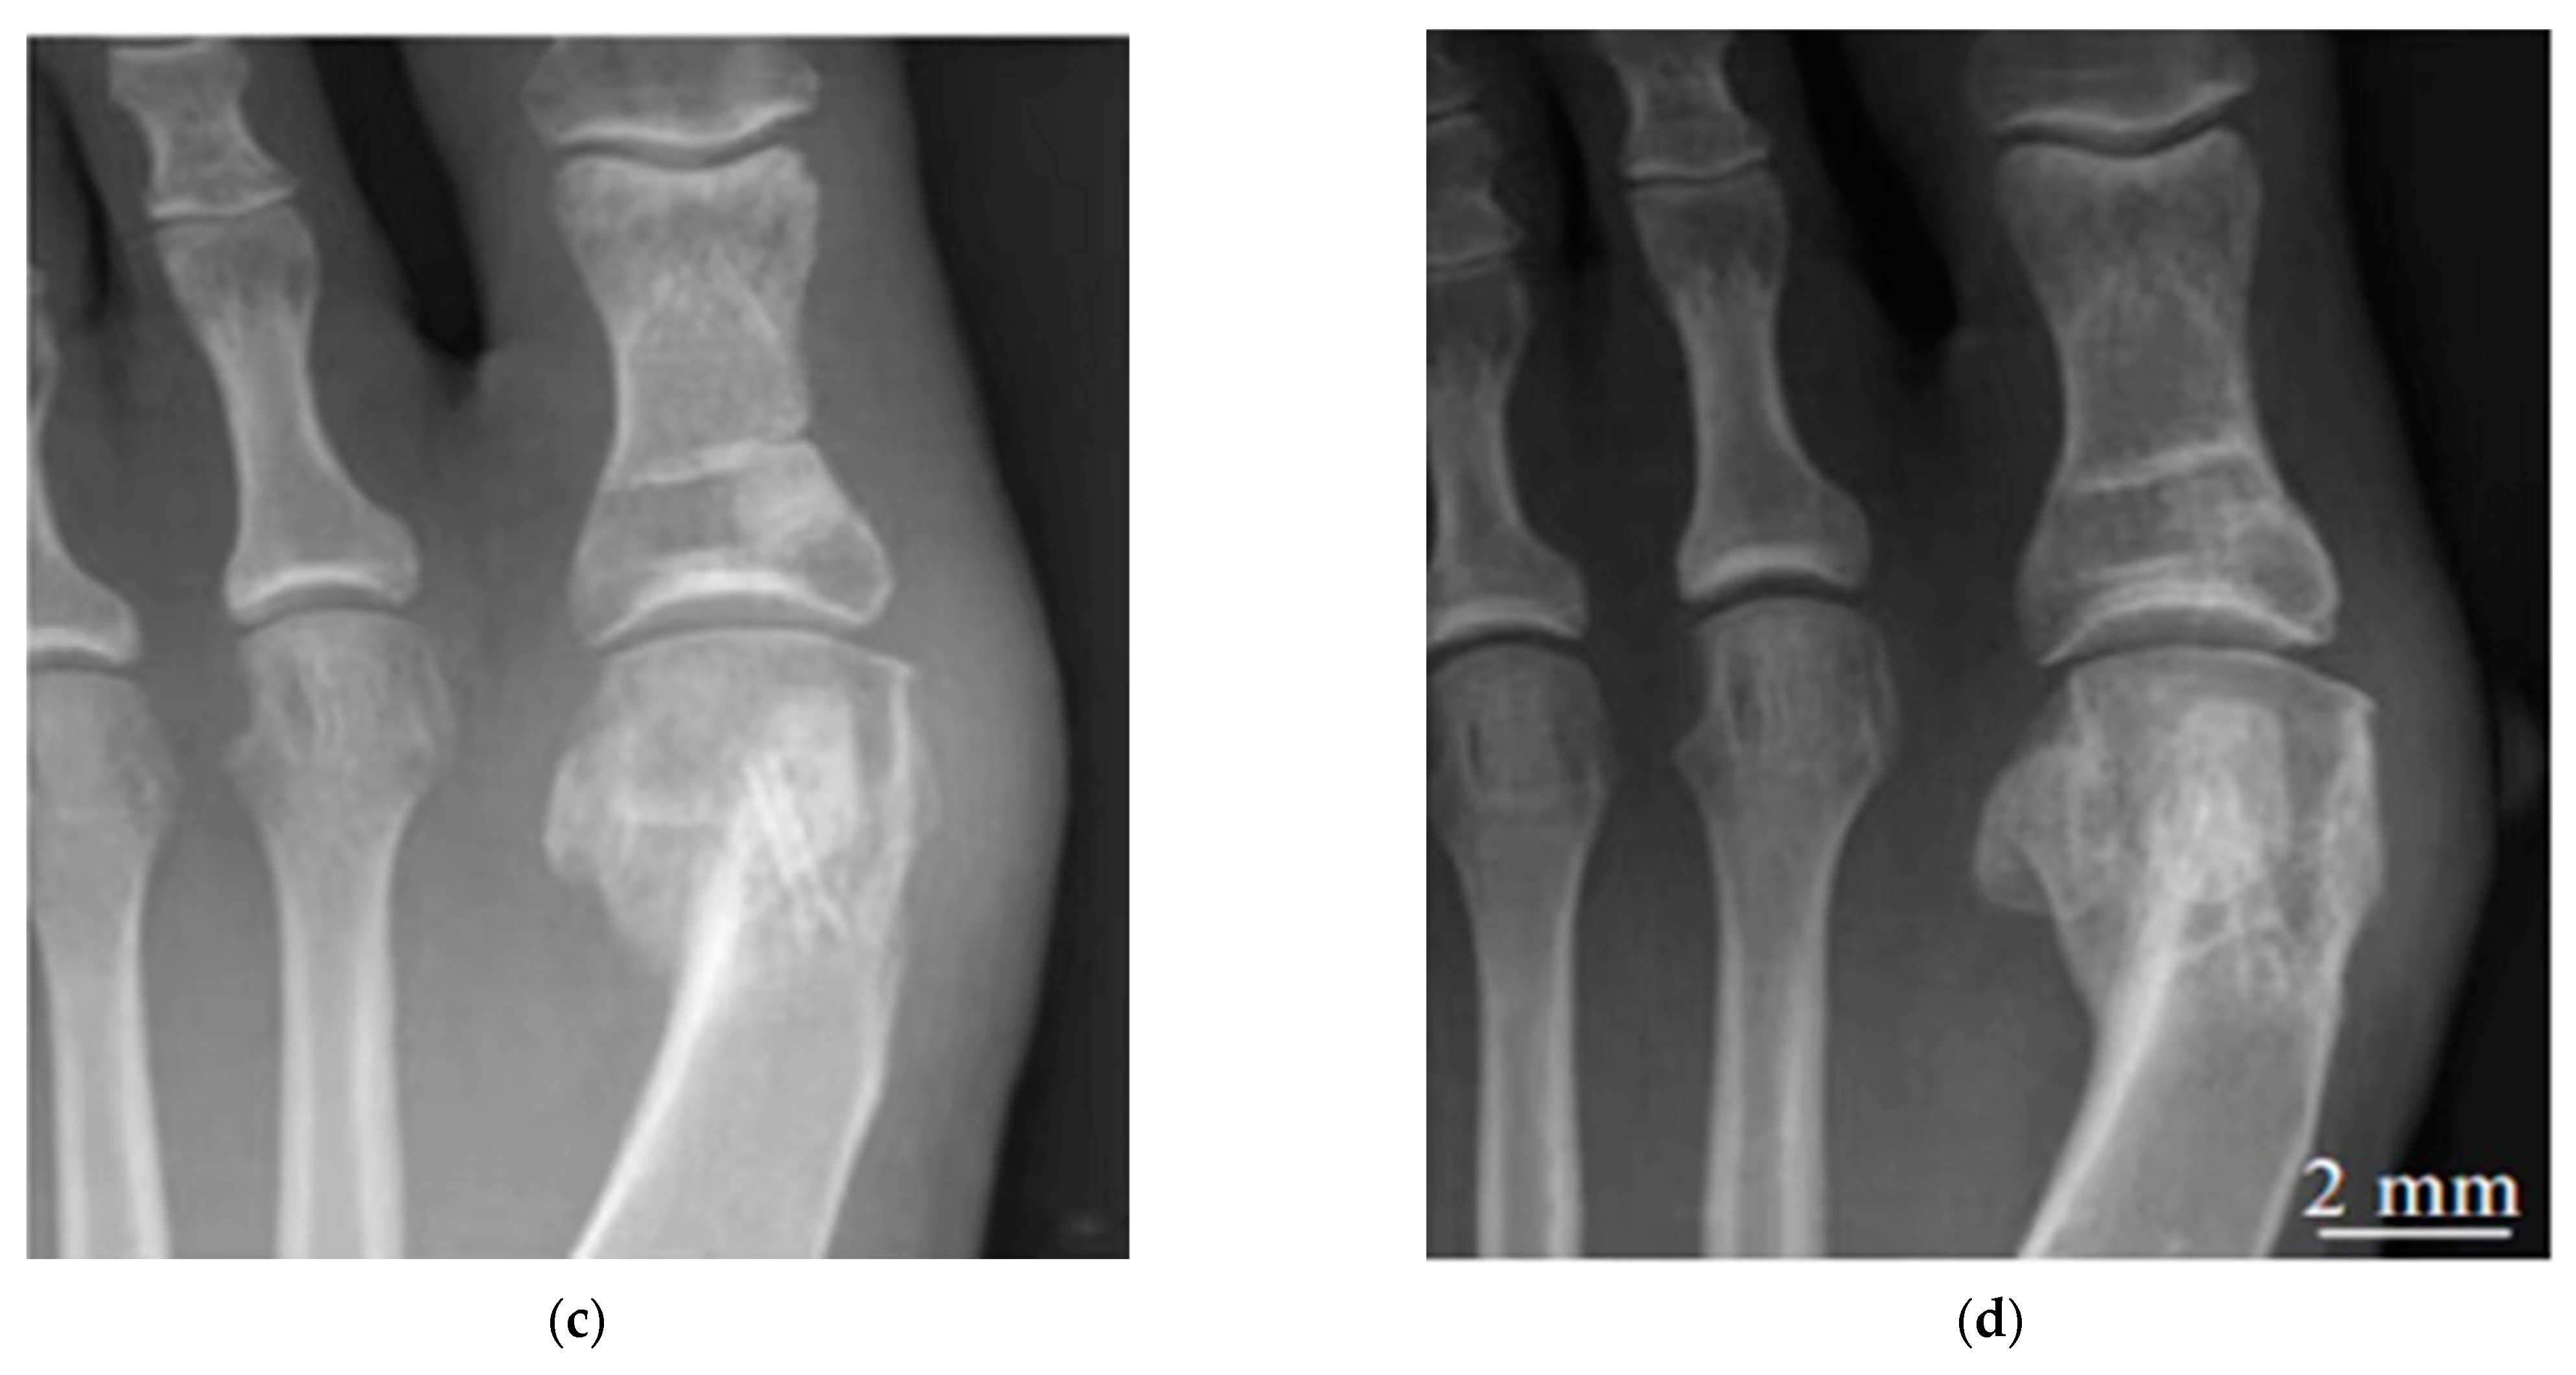

- Windhagen, H.; Radtke, K.; Weizbauer, A.; Diekmann, J.; Noll, Y.; Kreimeyer, U.; Schavan, R.; Stukenborg-Colsman, C.; Waizy, H. Biodegradable Magnesium-Based Screw Clinically Equivalent to Titanium Screw in Hallux Valgus Surgery: Short Term Results of the First Prospective, Randomized, Controlled Clinical Pilot Study. Biomed. Eng. Online 2013, 12, 62. [Google Scholar] [CrossRef] [PubMed]

- Plaass, C.; Ettinger, S.; Sonnow, L.; Koenneker, S.; Noll, Y.; Weizbauer, A.; Reifenrath, J.; Claassen, L.; Daniilidis, K.; Stukenborg-Colsman, C.; et al. Early Results Using a Biodegradable Magnesium Screw for Modified Chevron Osteotomies. J. Orthop. Res. 2016, 34, 2207–2214. [Google Scholar] [CrossRef]

- Seitz, J.M.; Lucas, A.; Kirschner, M. Magnesium-Based Compression Screws: A Novelty in the Clinical Use of Implants. JOM 2016, 68, 1177–1182. [Google Scholar] [CrossRef]

- Lee, J.W.; Han, H.S.; Han, K.J.; Park, J.; Jeon, H.; Ok, M.R.; Seok, H.K.; Ahn, J.P.; Lee, K.E.; Lee, D.H.; et al. Long-Term Clinical Study and Multiscale Analysis of in Vivo Biodegradation Mechanism of Mg Alloy. Proc. Natl. Acad. Sci. USA 2016, 113, 716–721. [Google Scholar] [CrossRef]

- Plaass, C.; von Falck, C.; Ettinger, S.; Sonnow, L.; Calderone, F.; Weizbauer, A.; Reifenrath, J.; Claassen, L.; Waizy, H.; Daniilidis, K.; et al. Bioabsorbable Magnesium versus Standard Titanium Compression Screws for Fixation of Distal Metatarsal Osteotomies—3 Year Results of a Randomized Clinical Trial. J. Orthop. Sci. 2018, 23, 321–327. [Google Scholar] [CrossRef]